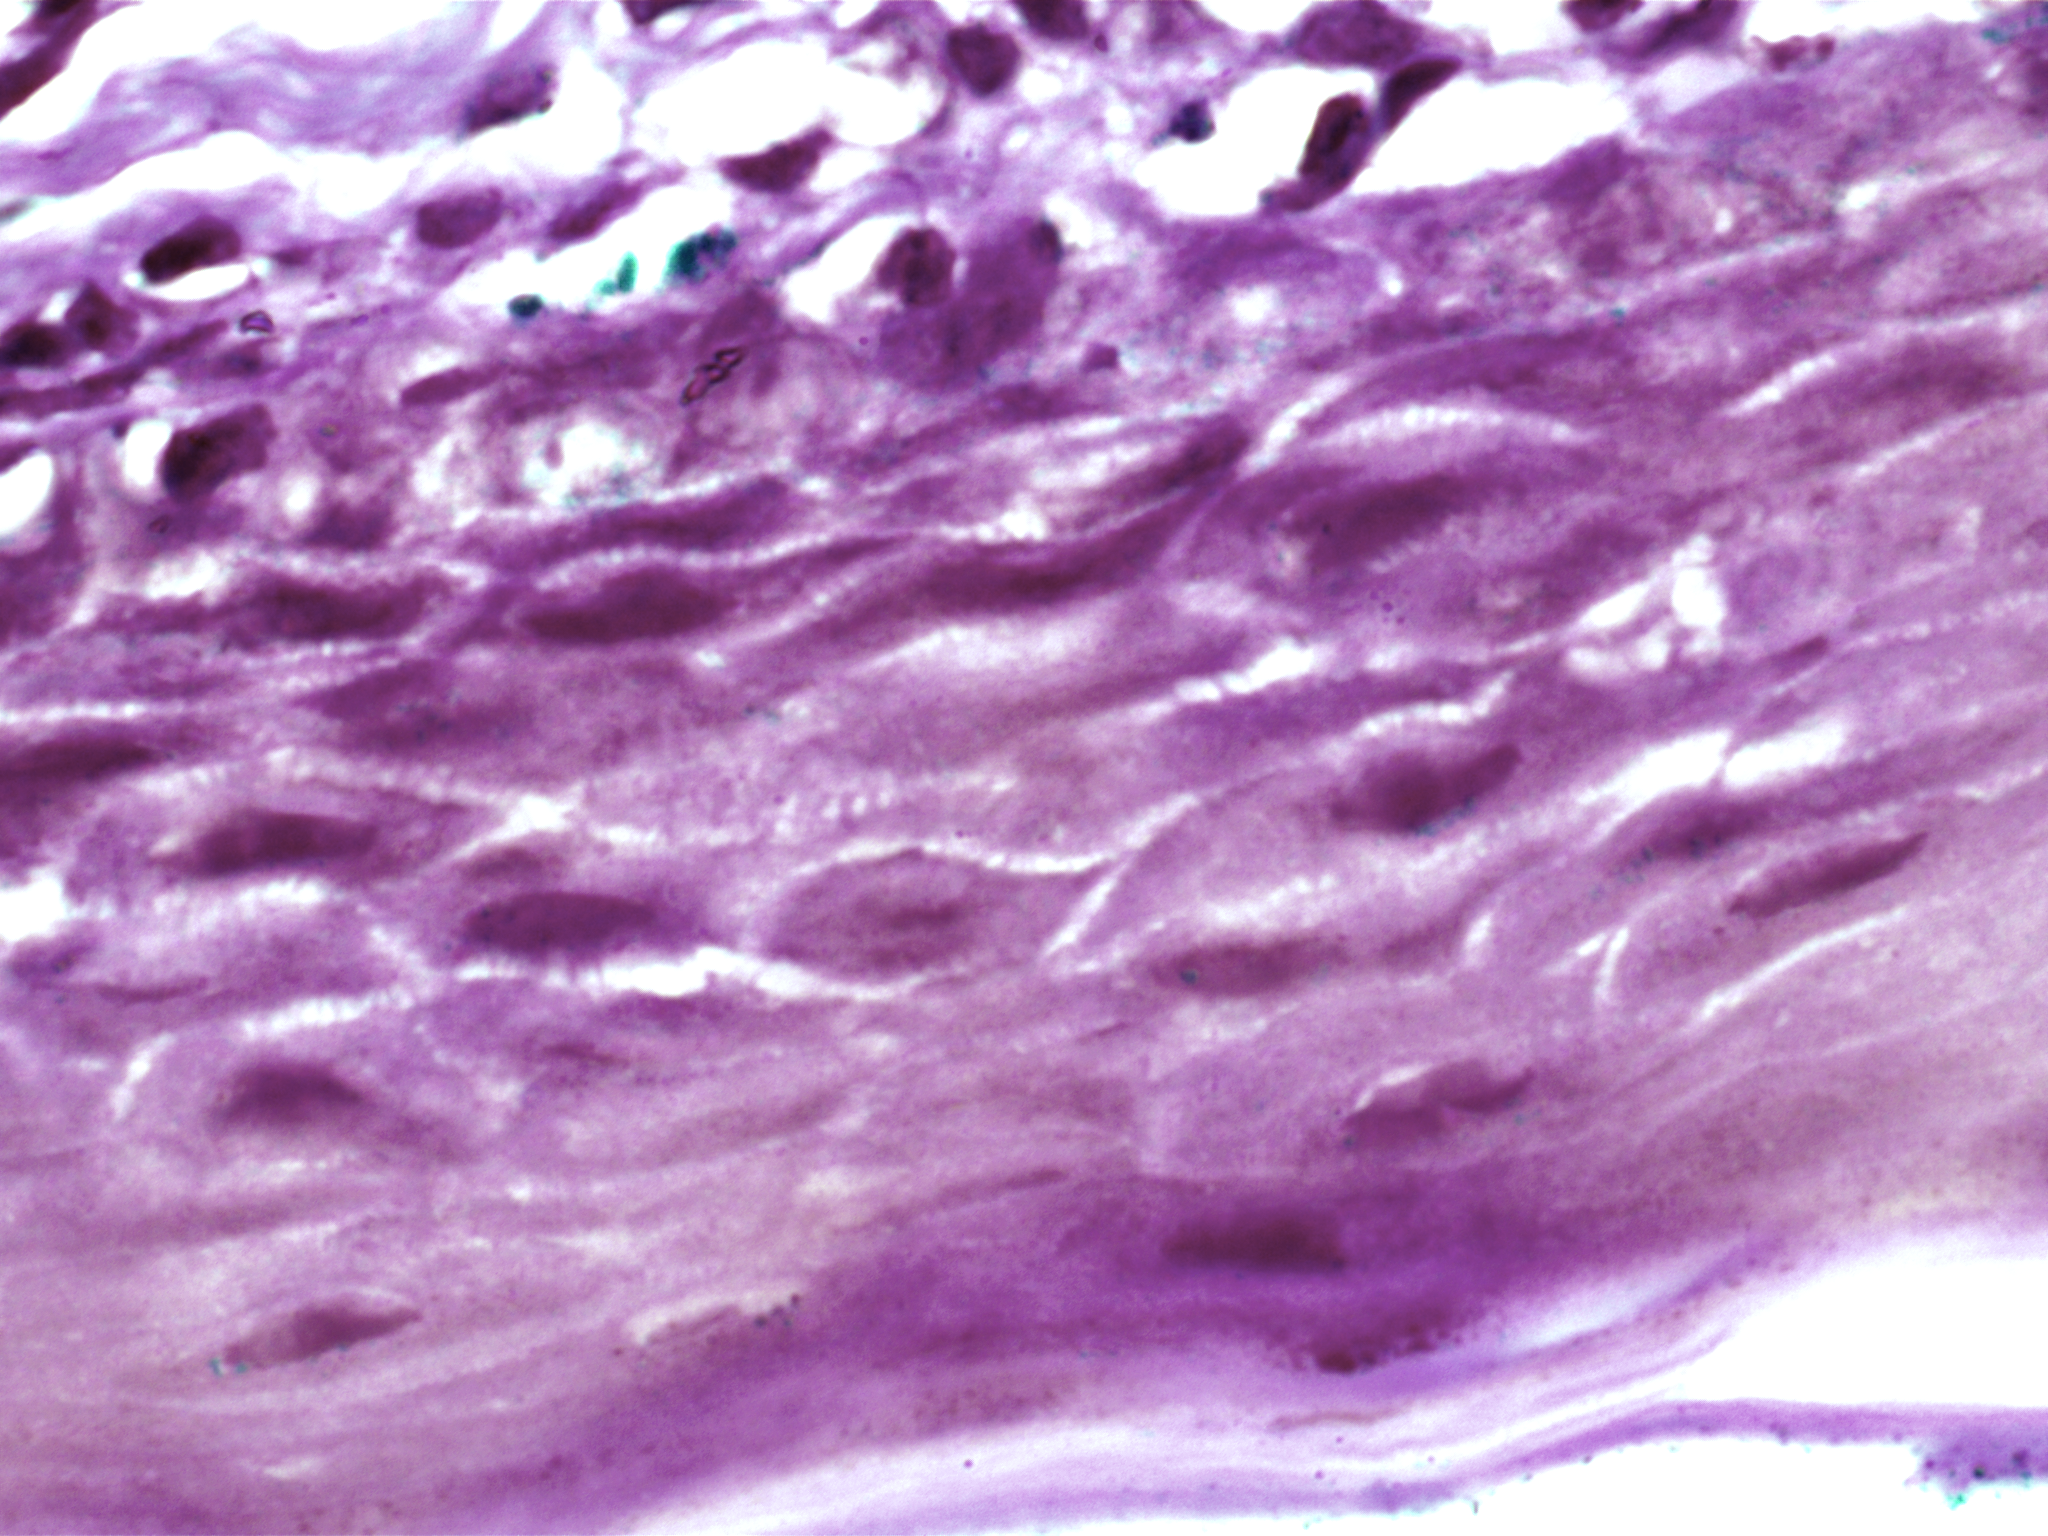

| Title: | High-resolution AI image dataset for diagnosing oral submucous fibrosis and squamous cell carcinoma |

| Description: | Oral cancer is a global health challenge with a difficult histopathological diagnosis. The accurate histopathological interpretation of oral cancer tissue samples remains difficult. However, early diagnosis is very challenging due to a lack of experienced pathologists and inter- observer variability in diagnosis. The application of artificial intelligence (deep learning algorithms) for oral cancer histology images is very promising for rapid diagnosis. However, it requires a quality annotated dataset to build AI models. We present ORCHID (ORal Cancer Histology Image Database), a specialized database generated to advance research in AI-based histology image analytics of oral cancer and precancer. The ORCHID database is an extensive multicenter collection of high-resolution images captured at 1000X effective magnification (100X objective lens), encapsulating various oral cancer and precancer categories, such as oral submucous fibrosis (OSMF) and oral squamous cell carcinoma (OSCC). Additionally, it also contains grade-level sub-classifications for OSCC, such as well- differentiated (WD), moderately-differentiated (MD), and poorly-differentiated (PD). The database seeks to aid in developing innovative artificial intelligence-based rapid diagnostics for OSMF and OSCC, along with subtypes. |

| Imaging Type: | Histopathology (HISTO) |

| Imaging Sub-type: | Diagnostic Pathology |

| The ORCHID database is an extensive multicenter collection of high-resolution images captured at 1000X effective magnification (100X objective lens). Tissue slides were collected with the approval of an ethical committee from the participating hospitals and research institutions. The buccal mucosa tissue samples were collected for three classes, normal, OSMF, and OSCC, with grade-wise annotation from the pathologists at each hospital. Biopsy samples of normal, OSMF and OSCC tissues underwent H&E staining. The staining procedure was conducted either in-house or outsourced to different laboratories. To eliminate staining variations across different laboratories, the preparation of H&E slides involved five histopathology labs, each utilizing their own independently developed and optimized protocols for the staining process. Following staining, the samples were examined under a microscope by a skilled histopathologist to assess cellular morphology, and tissue architecture, and identify any distinctive features or abnormalities specific to each sample type. This evaluation by the histopathologist involved grading the tissue slides for OSCC and OSMF, as well as differentiating between normal and diseased tissue sections. Images were acquired using a 1000X magnification (100X objective) lens from Leedz microimaging (LMI) bright field microscopy. To capture the images consistently, we utilized ToupView imaging software, which was configured for automatic adjustments. This setting applies to both white balance and camera settings, thereby standardizing the image acquisition process across different slides. The images of the H&E stained slides were captured at 1000X magnification(100X objective lens). By setting the ToupView software to automatically adjust white balance and camera settings, we aimed to minimize human intervention and the variability it introduces. This approach ensures that the images are not only consistent but also replicable in different laboratory settings, provided similar equipment and software settings are used. We collected approximately 100–150 images per tissue slide, which were stored in PNG file format. |